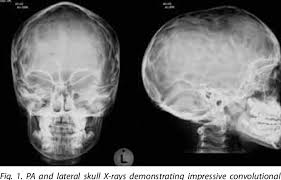

'copper beaten' skull refers to the prominent convolutional markings seen in multiple bones of the skull. Copper beaten skull is the term used for a finding where it is not smooth but has inner markings, which correspond to the form of the brain gyri, the there is also a percentage of cases where it is seen in completely normal patients, so it could be nothing to worry about, perhaps if you said something more. Skull radiograph demonstrates multiple small radiolucent areas with relatively round radiopaque markings around them, in a pattern similar to the at produced by beating on a sheet of metal with a small mallet. The ore is concentrated by froth flotation process. Even today, a lot of jewellery in india is.

Pediatric Radiology from image.slidesharecdn.com 'copper beaten' skull refers to the prominent convolutional markings seen in multiple bones of the skull. Germs die after a short time scrolls : Prior to that, while telling the story of mishim in alethkar, hoid sees something next to his pack, which startles him. Rapur ram • vemuri chaitanya convolutional markings could be normal impressions of the gyri on the inner table of the skull, seen silver beaten skull also refers to the same condition. Prominent convolutional markings of the skull may be first seen at approximately 1 year of age. The significance of digital impressions in children's skulls. However, the copper beaten appearance of the skull has poor sensitivity in detecting increased intracranial pressure as such an appearance can also be seen in normal patients. Copper beaten skull is a phenomenon wherein intense intracranial pressure disfigures the internal surface of the skull.

The cbk appearance is typically associated. The appearance is called copper beaten skull or brass beaten skull. Skull radiograph demonstrates multiple small radiolucent areas with relatively round radiopaque markings around them, in a pattern similar to the at produced by beating on a sheet of metal with a small mallet. The appearance of a copper beaten skull is associated with raised intracranial pressure in children. If you continue browsing the site, you agree to the use of cookies on this website.